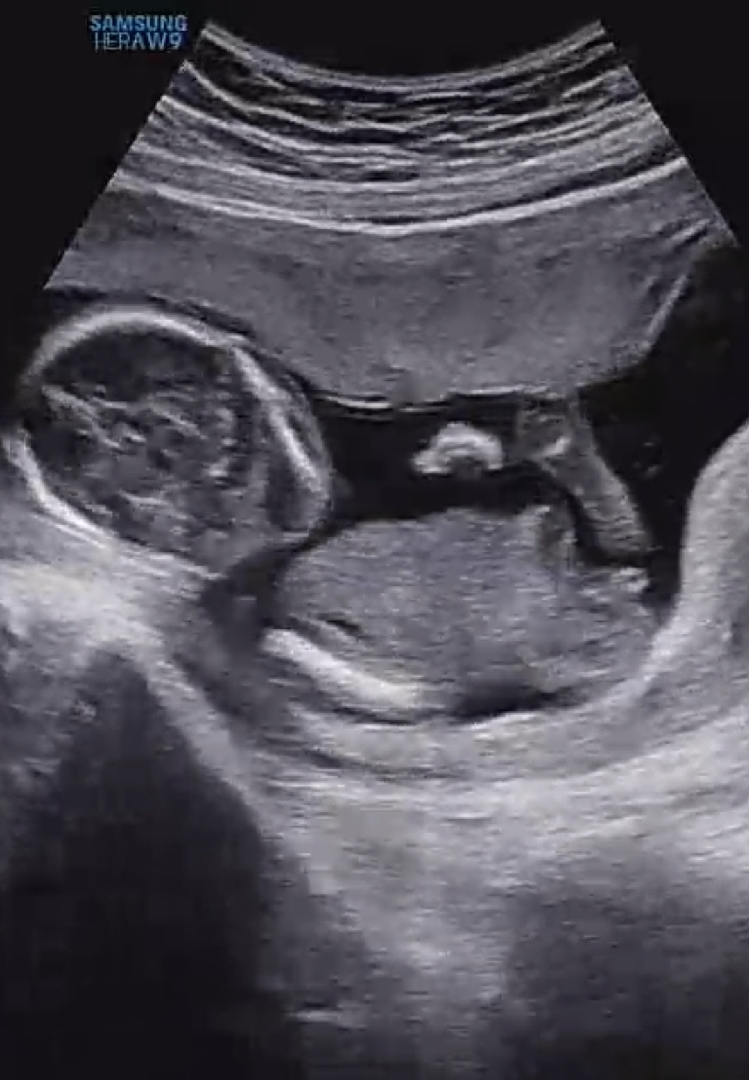

12주때 딸 확률 70프로라 하셨어요ㅌㅋㅋ 전 완전 굳게 이번엔 아들일거라 생각했고.....아들이었움 좋겠다고 했는데😂 🌶맞을까여???!?!?!?!?!?🙏🙏🙏🙏 막 인터넷 찾아보고 여기저기 카페 둘러보고 남자아기 촘파로 🌶보이는거만 찾아봤는데 모양이 은근 비슷해서요🥹🥹🥹

각도법1도모르지만 니프티로 아들확정인데 비교햐보세용 ㅠㅠ

각도법으론 여아 같은데요..!!! 🤔

각도법이 안보이는 사진입니다🤣 저건 앞모습이라!! 12주 각도법에선 완전 딸이여 보이긴 했네여..ㅠㅠ